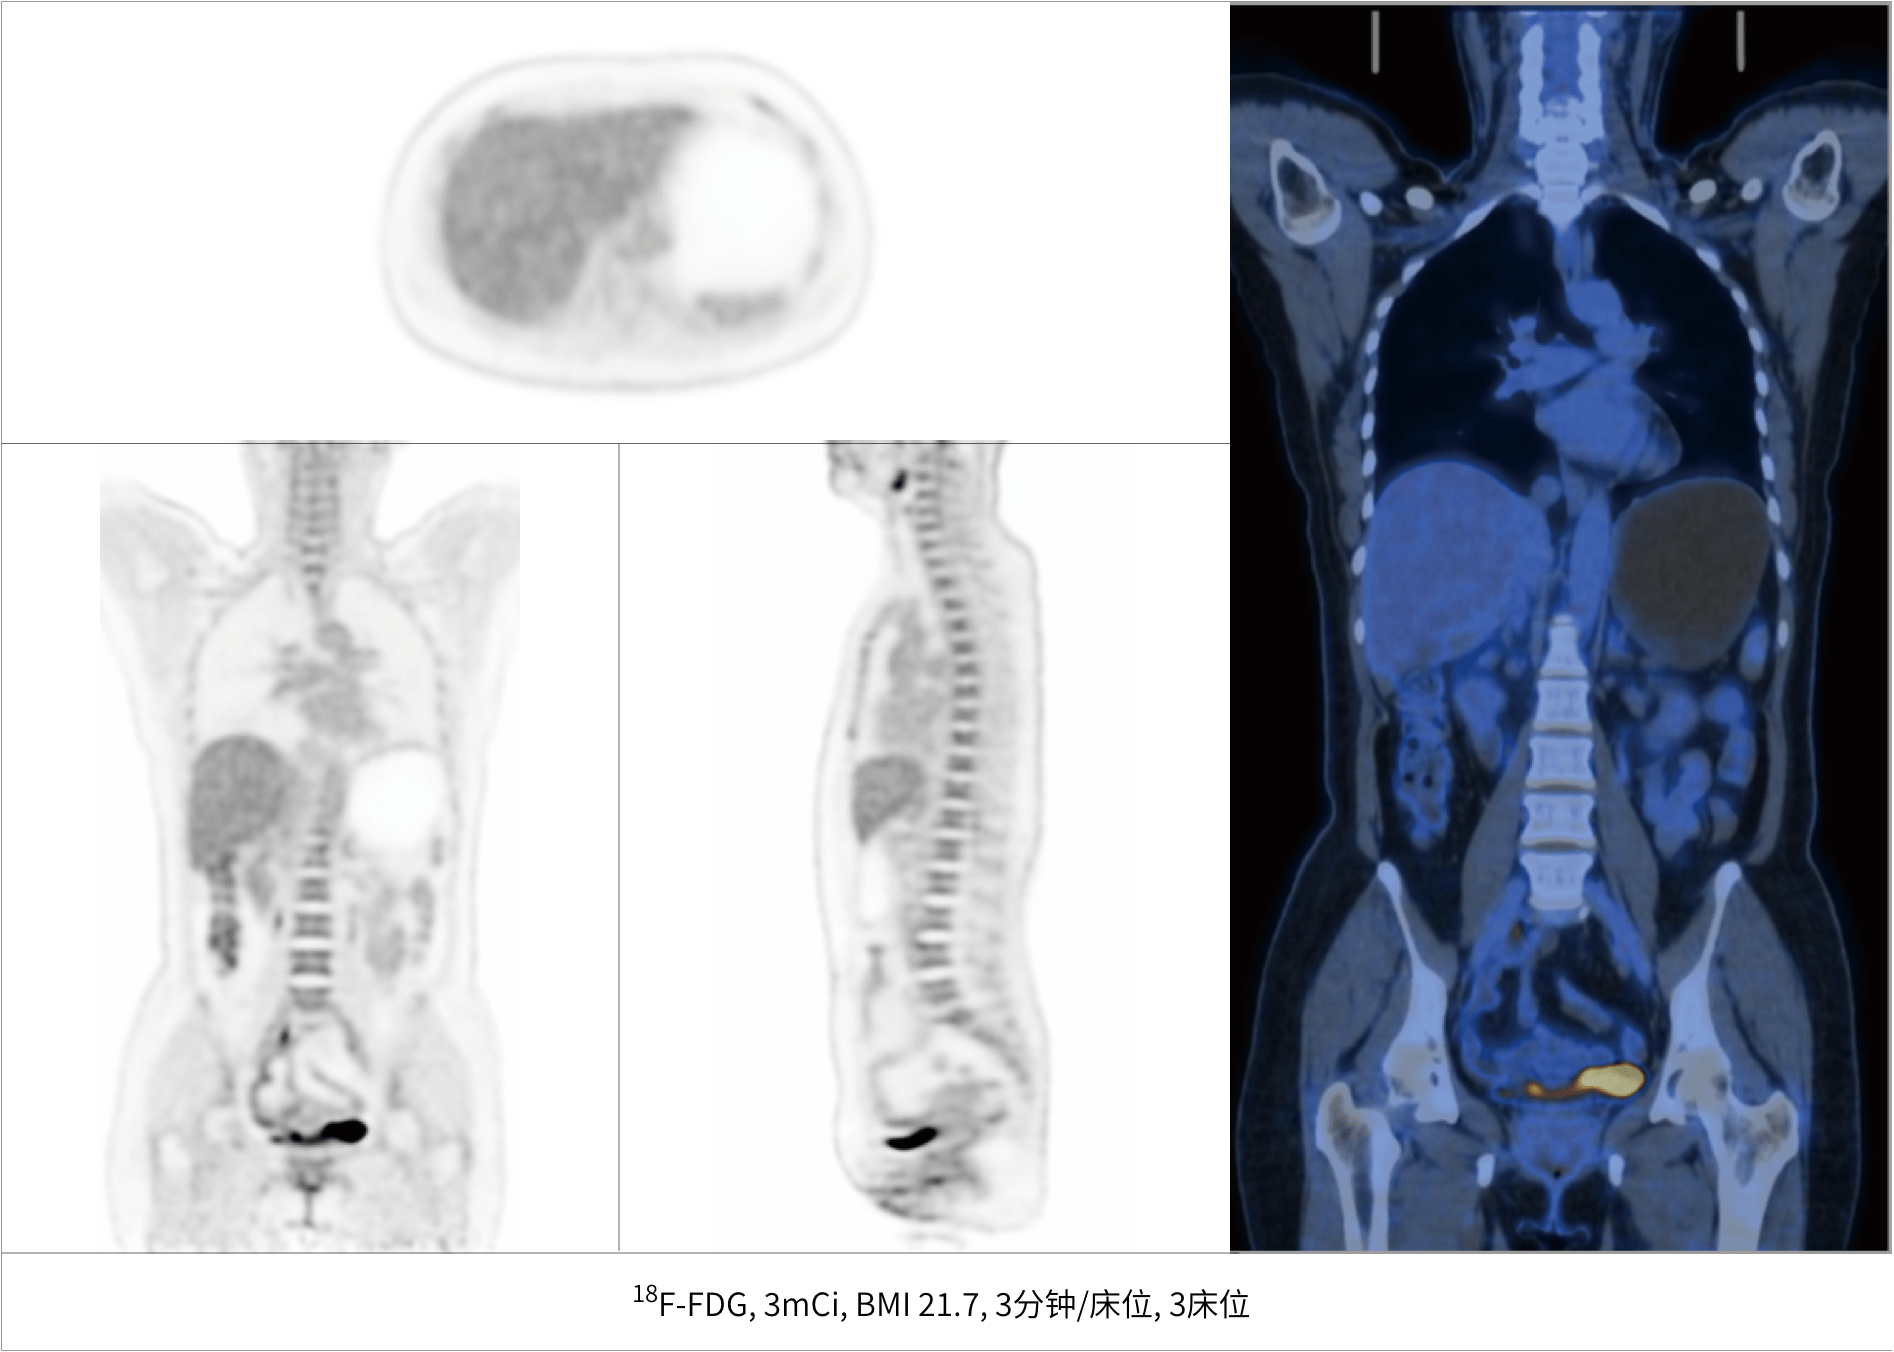

微小病灶无以遁形